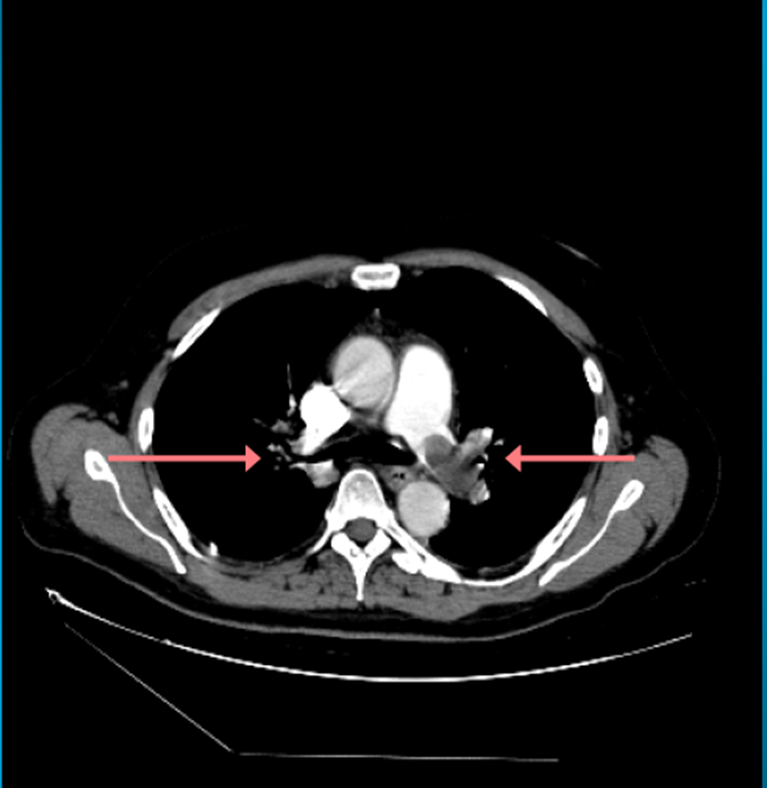

Akciğer damarlarında pıhtı şüphesinde hızlı değerlendirme ve takip.

Risk faktörleri, görüntüleme bulguları ve ileri değerlendirme süreçleri.